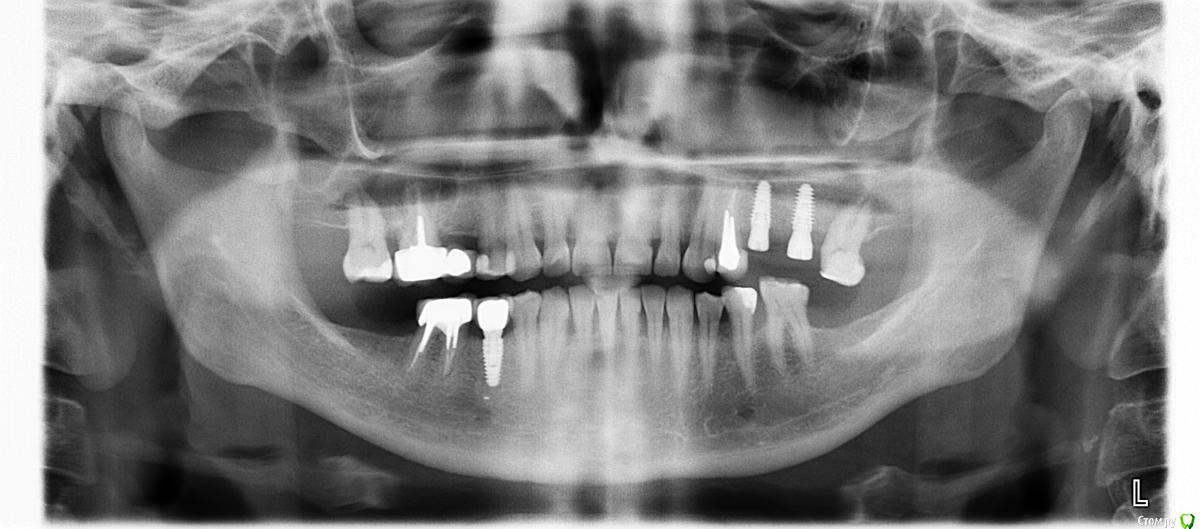

TIGER Опубликовано 23 января, 2018 Поделиться Опубликовано 23 января, 2018 Здравствуйте. Нужен совет по порядку действий. Ранее был синуслифтинг слева, потом имплантация и протезироване. После протезирования через месяц произошло отторжение имплантата по месту 26 (на момент осмотра он был подвижен)Убрал имплантат, через ложе имплантата убрал "кашу" из синуса, перфорации пазухи нет, по ощущениям костный материал частично прикреплен к слизистой пазухи (он не отрывается но в то же время движется вместе со слизистой). Отмыл, положил коллагеновую губку.Скажите, как дальше вести пациента. Как после удаления, либо отслоиться, через лунку еще раз все убрать внести остеопластический материал и ушить наглухо(сообщения с пазухой нет)?ОПТГ.jpgодиночные были коронки? Ссылка на комментарий

gum Опубликовано 31 января, 2018 Автор Поделиться Опубликовано 31 января, 2018 Сделали КТ, качество не очень хорошее. По клинике жалоб нет, не отслоился от мед стенки (понимаю, что ошибка, но на сколько критично?) плюс пазуха отреагировала утолщением слизистой.Подскажите как дальше вести пациента? Ссылка на комментарий